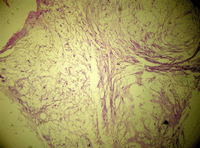

A 14-year-old boy from Mojo, an industrial town located 70 km from the capital of Ethiopia - Addis Ababa - on the way to Djibouti; presented in Adama Hospital with 3 days history of abdominal pain, nausea, vomiting ingested materials, and inability to pass flatus. He gave a history of presenting several times to a nearby clinic with long standing changing bowel habit, abdominal discomfort, anorexia, weight loss, weakness and constipation before developing the current signs and symptoms of acute abdomen. There was no history of a similar illness in the family. Laparotomy was done for acute abdomen and intraoperatively a mass of 8 by 6 cm was found in the ascending colon with signs of obstruction and omental deposit. Excision of the mass and colostomy were done. A month later the patient was referred to our oncology center with a biopsy result which confirmed poorly differentiated mucinous adenocarcinoma (Figure 1). On physical examination he had a good performance status, stable vital signs, a healed post-operative midline scar, a well functioning colostomy and normal rectal examination. Metastatic workup did not show any signs of metastasis. A tumor marker for gastrointestinal tumor Carcinoembrionic antigen (CEA) was 150 ng/ml.

Figure 1. Histopathology of mass from ascending colon.  Poorly differentiated mucinous adenocarcinoma.